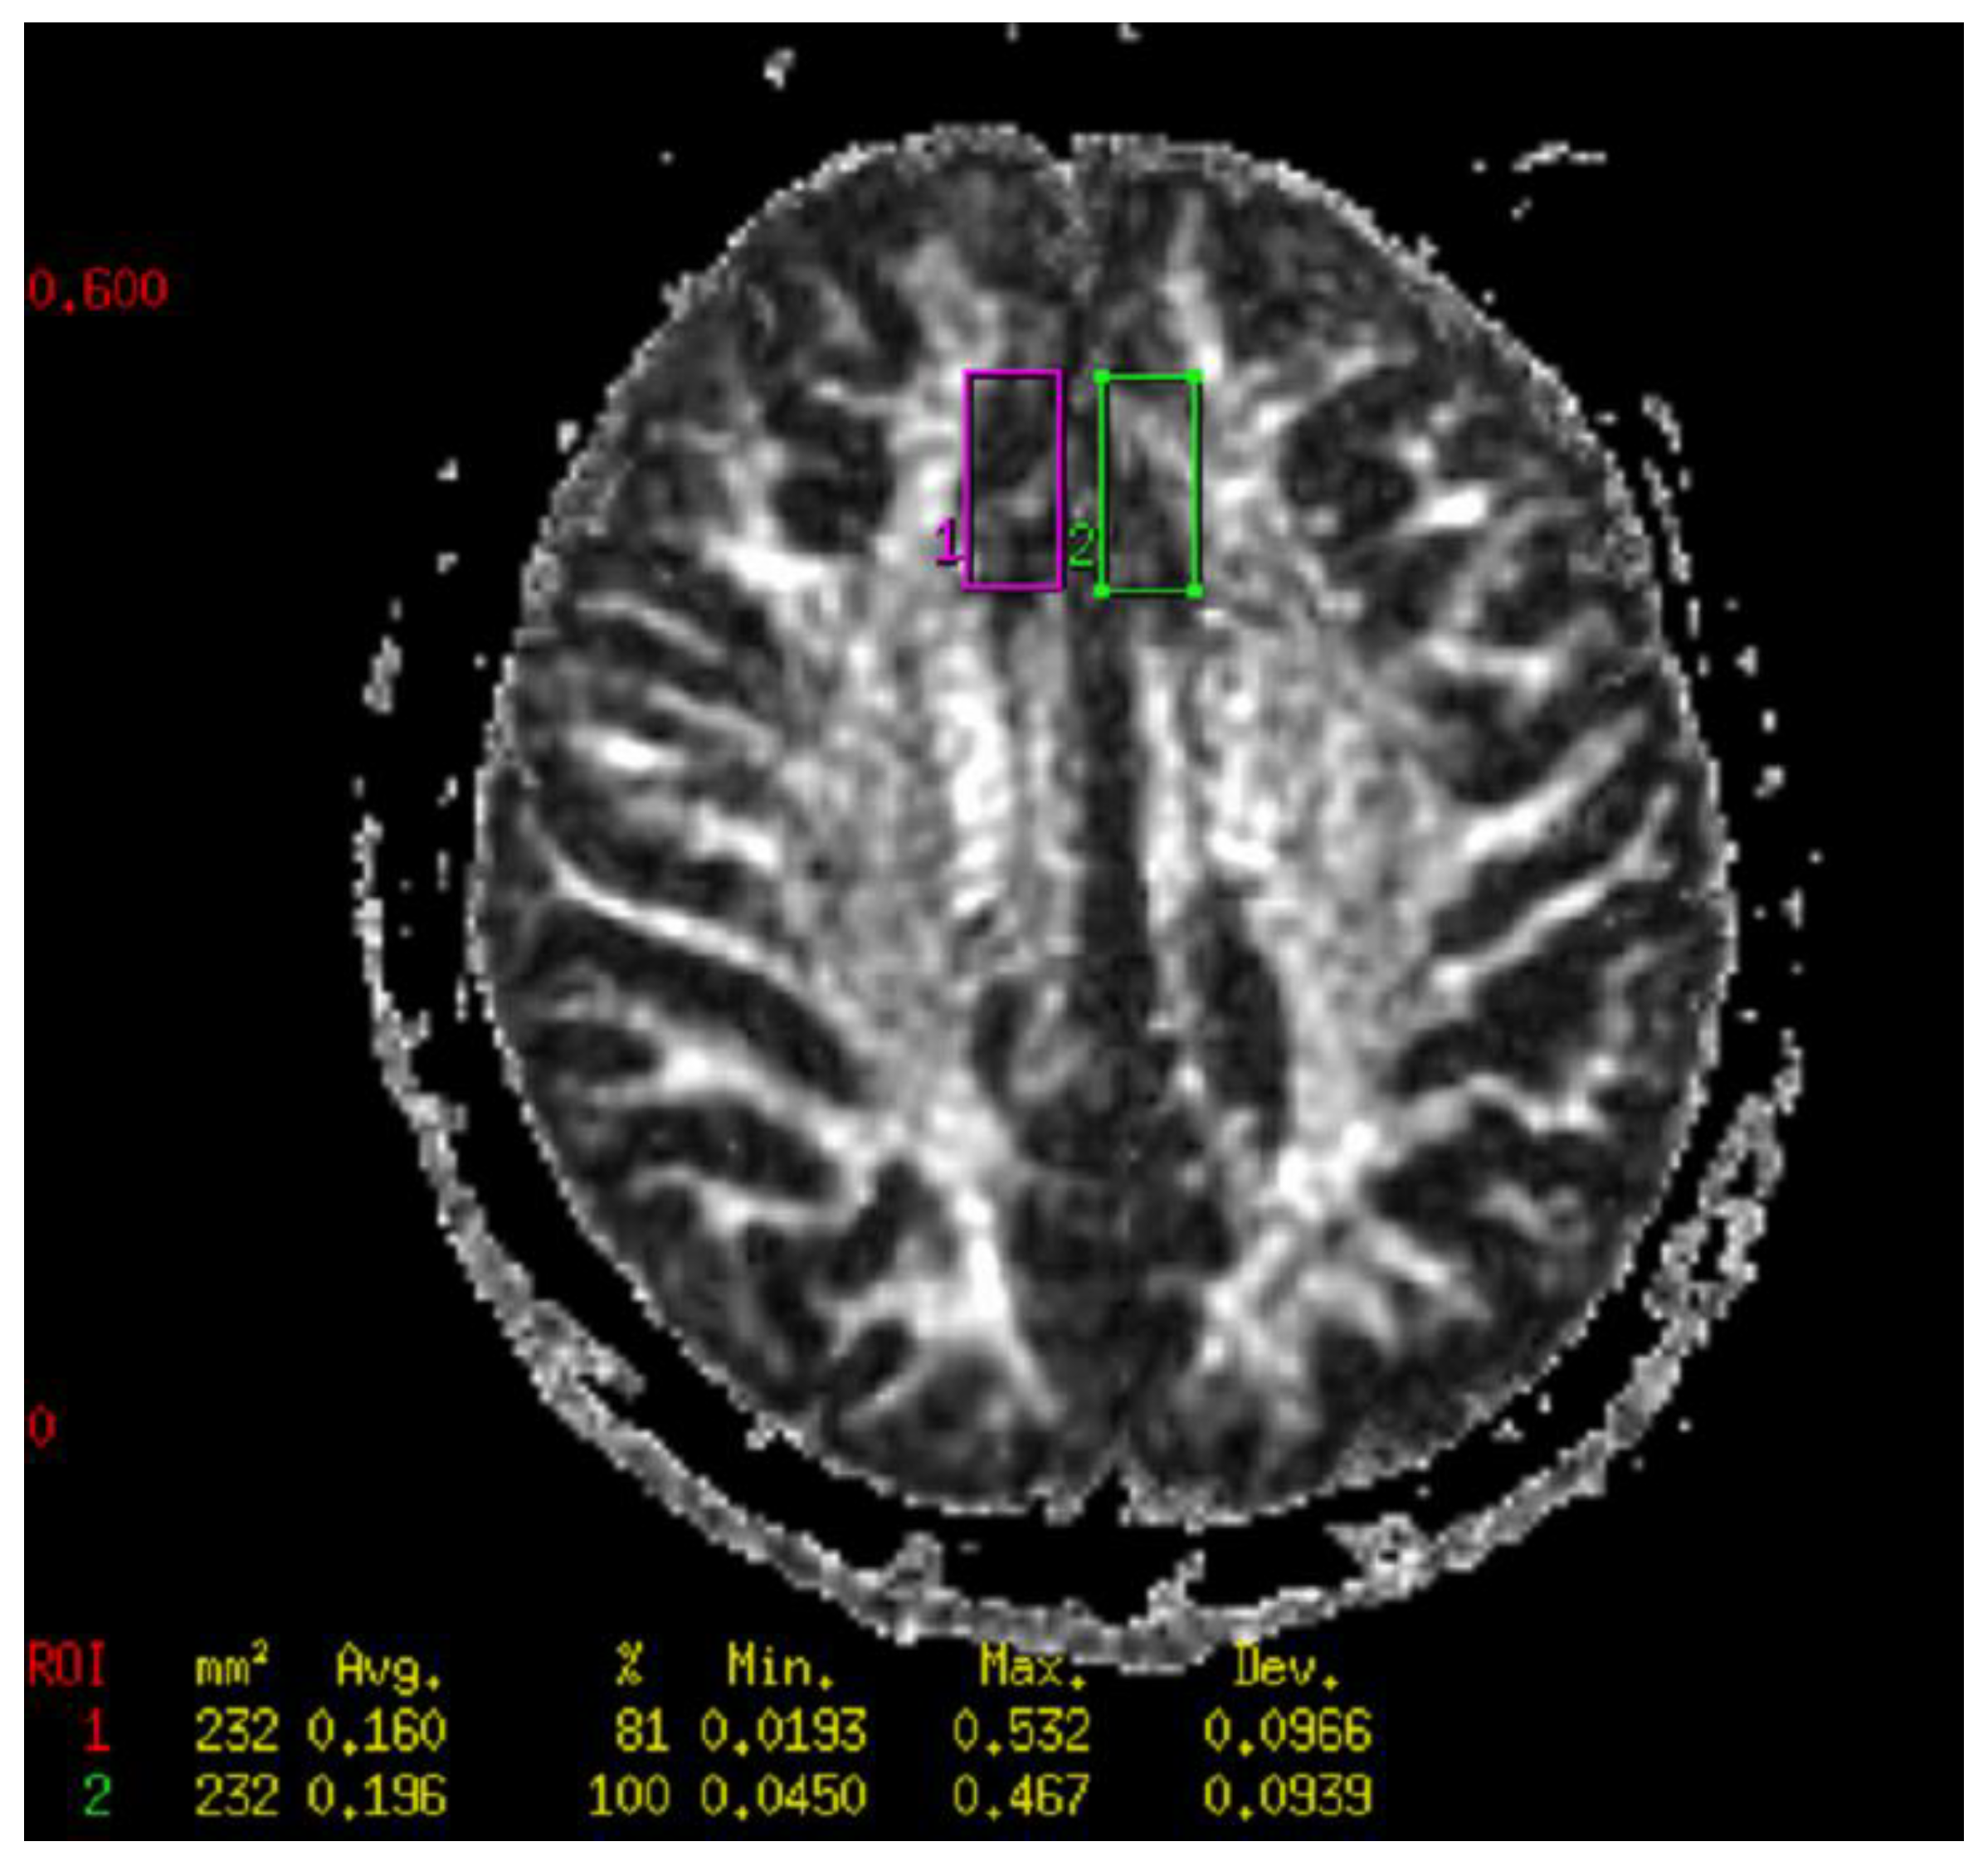

4.6. Neuroimaging Analysis